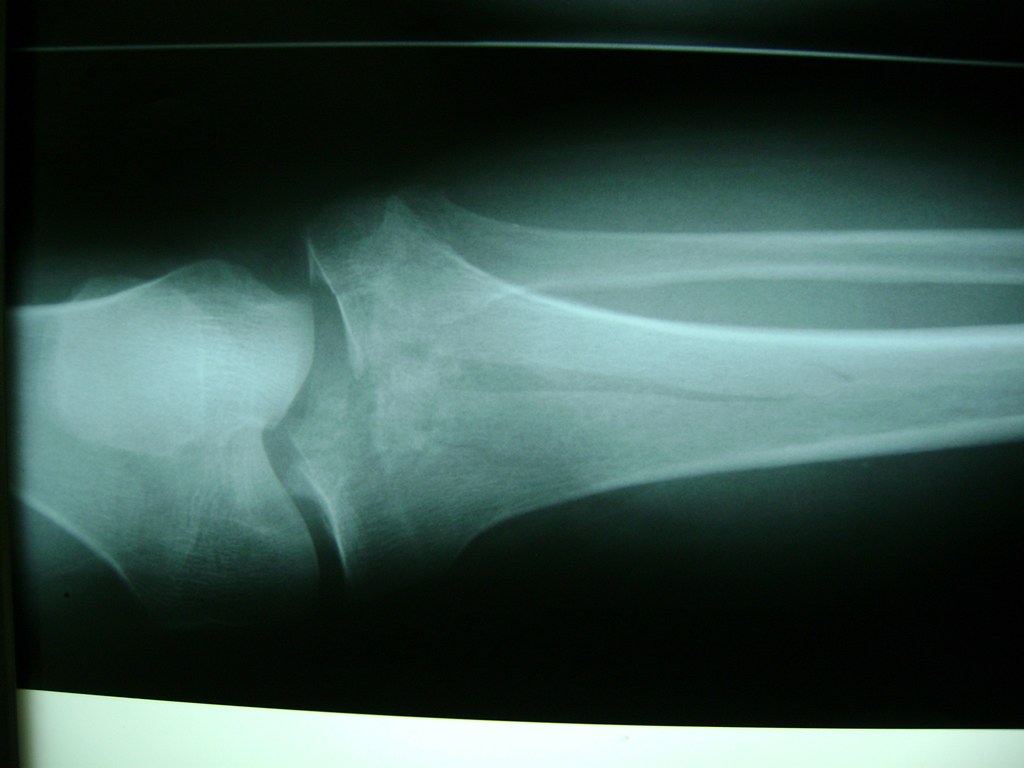

Tendón de Aquiles

La artroscopia de rodilla es un cirugía en el cual la estructura interna de la articulación es examinada ya sea para realizar un diagnostico o para realizar un tratamiento, este procedimiento se realiza utilizando un instrumento parecido a un pequeño tubo llamado artroscopio.